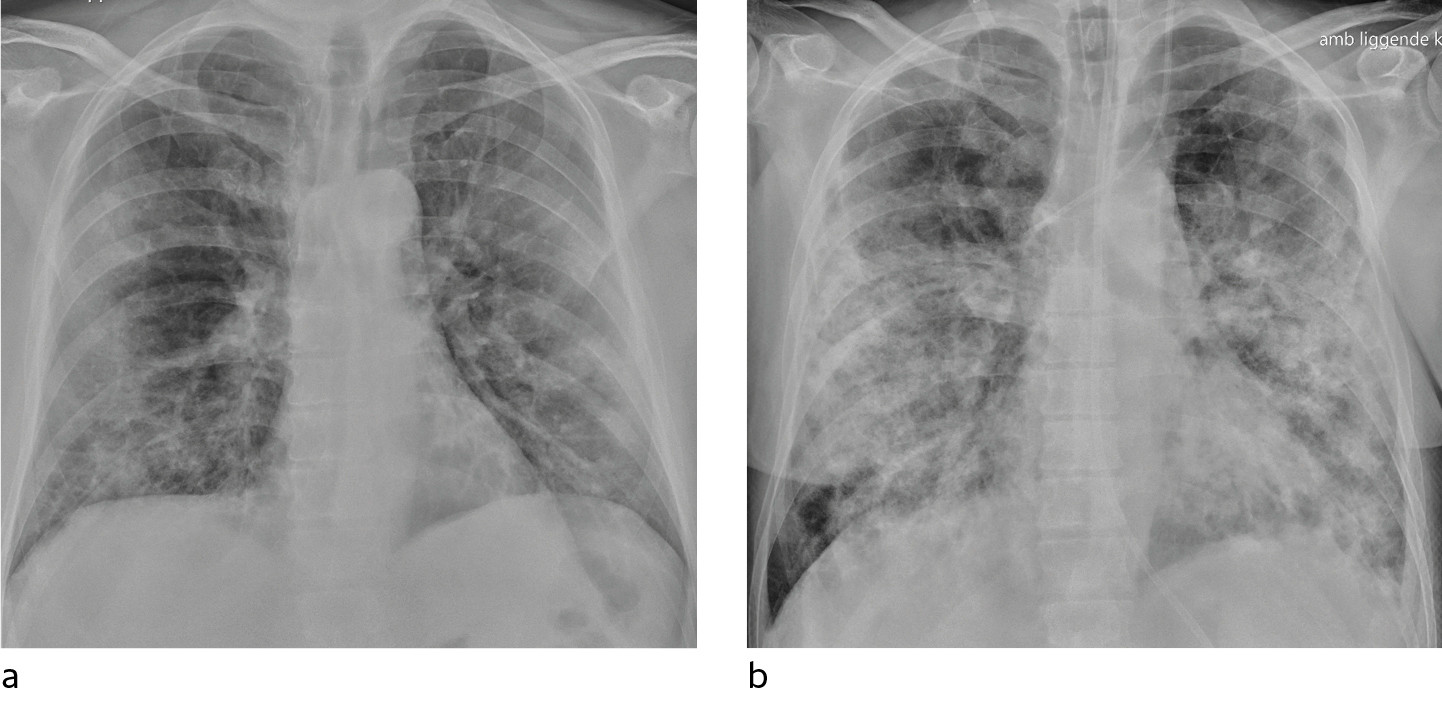

In a dataset from Hong Kong, 69 % had findings on chest X-rays prior to treatment (baseline), but 9 % had findings on chest X-ray prior to positive PCR (14). Sensitivity for chest X-ray was 69 % and for PCR 91 %. The most common X-ray findings were bilateral consolidation and ground-glass opacities with peripheral and caudal distribution. The findings were most pronounced 10–12 days after the onset of symptoms. Figures 1 and 2 show typical chest X-ray patterns in patients with COVID-19.

For inpatients, a bedside X-ray image at an early stage of the disease may be useful as a basis of comparison for interpreting later images. In patients with severe disease, bedside X-rays will be indicated to check technical medical equipment (Figure 3), but daily, routine chest X-rays are not indicated for stable patients. In the course of the disease, bedside X-ray will be indicated on suspicion of complications and for following up and monitoring the progression of the disease.

Typical CT findings vary with symptom duration and can be divided into three stages: an early phase, an intermediate phase that extends from 3–5 days after symptom onset, and a late phase.

There are not always CT findings the first few days after symptom onset. In a material with symptomatic, but unspecified patients, 56 % had normal CT findings within two days of symptom onset (12), declining to 9 % 3–5 days after symptom onset and 4 % 6–12 days after symptom onset. The frequency of findings varies with the severity of the disease. Initial diagnostic imaging yielded normal findings for 18 % in a cohort of patients who were not severely ill, but in only 3 % of patients who were (15). Typical CT findings are multiple, bilateral ground-glass opacities with peripheral distribution, most frequently located in the lower lobes. In the intermediate phase there are increasing amounts of consolidation and affection of several lobes, and increased septation with crazy paving as sign of interstitial affection. In the late phase there is increasing total extension, but ground-glass opacities and consolidation are still the dominant findings (12, 16). Figures 4, 5 and 6 show typical CT findings in different phases of COVID-19.